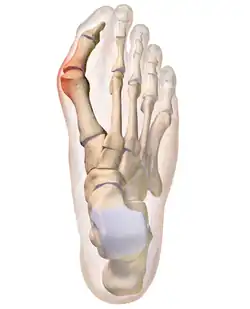

The bump itself is due to the head of the metatarsal partly due to the swollen bursal sac or an osseous (bony) anomaly on the metatarsophalangeal joint. The larger part of the bump is a normal part of the head of the first metatarsal bone that has tilted sideways to stick out at its distal (far) end (metatarsus primus varus).

Bunions are commonly associated with a deviated position of the big toe toward the second toe, and the deviation in the angle between the first and second metatarsal bones of the foot. The small sesamoid bones found beneath the first metatarsal (which help the flexor tendon bend the big toe downwards) may also become deviated over time as the first metatarsal bone drifts away from its normal position. Osteoarthritis of the first metatarsophalangeal joint, diminished or altered range of motion, and discomfort with pressure applied to the bump or with motion of the joint, may all accompany bunion development. Atop of the first metatarsal head either medially or dorso-medially, there can also arise a bursa that when inflamed (bursitis), can be the most painful aspect of the process.